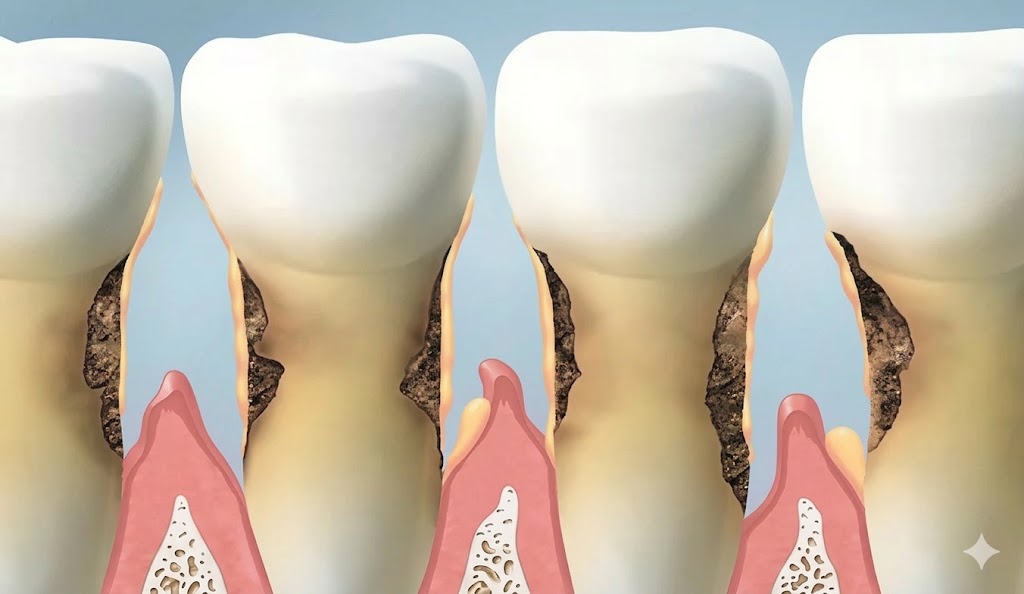

Gum disease — also called periodontal disease — is one of the most common chronic conditions in the United States, yet most patients don't know they have it until significant damage has already occurred. Unlike a cavity, which usually hurts, gum disease is largely painless in its early and middle stages. By the time it becomes uncomfortable, irreversible bone loss is often already underway.

Adult teeth should not feel loose. If you notice any mobility — even subtle movement when you press on a tooth — it means the supporting structures (bone and periodontal ligament) have been damaged significantly. Bone loss is the direct cause of tooth mobility in periodontal disease.

Similarly, if your bite has changed, or if teeth that were previously aligned have drifted apart or developed gaps, periodontal disease may be the cause. This degree of progression requires urgent evaluation — the goal is to preserve the remaining bone and prevent tooth loss.